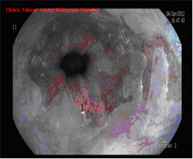

Diagnosis is performed using high-resolution magnification endoscopy (image enhancement), employing additional chromoendoscopy techniques conducted by endoscopists specialised in the early diagnosis of premalignant lesions, with targeted biopsies for analysis.

The HALO radiofrequency ablation system safely and uniformly ablates the oesophageal mucosa to a depth of approximately 1 mm. Ablation is a technique in which tissue is heated until it is no longer viable or alive. HALO technology is a very specific type of ablation where heat energy is applied precisely and in a controlled manner. Clinical trials have demonstrated that Barrett's tissue can be completely eliminated with HALO ablation technology in 98.4% of patients.